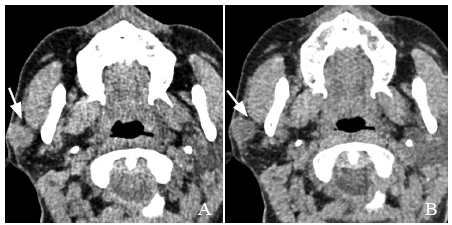

图1 男,38岁,多形性腺瘤。常规平扫示左侧腮腺类圆形占位,边界清晰,密度均匀,CT值约44.4 HU(箭,A);虚拟平扫示病灶边界清晰,密度均匀,平扫CT值约45.0 HU(箭,B)

2.2 常规平扫与虚拟平扫图像质量比较 2.2.1 客观图像评价 虚拟平扫噪声小于常规平扫,但 差异无统计学意义(P>0.05);虚拟平扫SNR 大于常规平扫,差异有统计学意义(P<0.05),见表2。2.2.2 主观图像评价 常规平扫与虚拟平扫图像的质 量评分差异无统计学意义(P>0.05),见表3。虚拟平扫与常规平扫对腮腺肿块数量、形态、边缘、坏死囊变及钙化显示情况见表4 及图1。